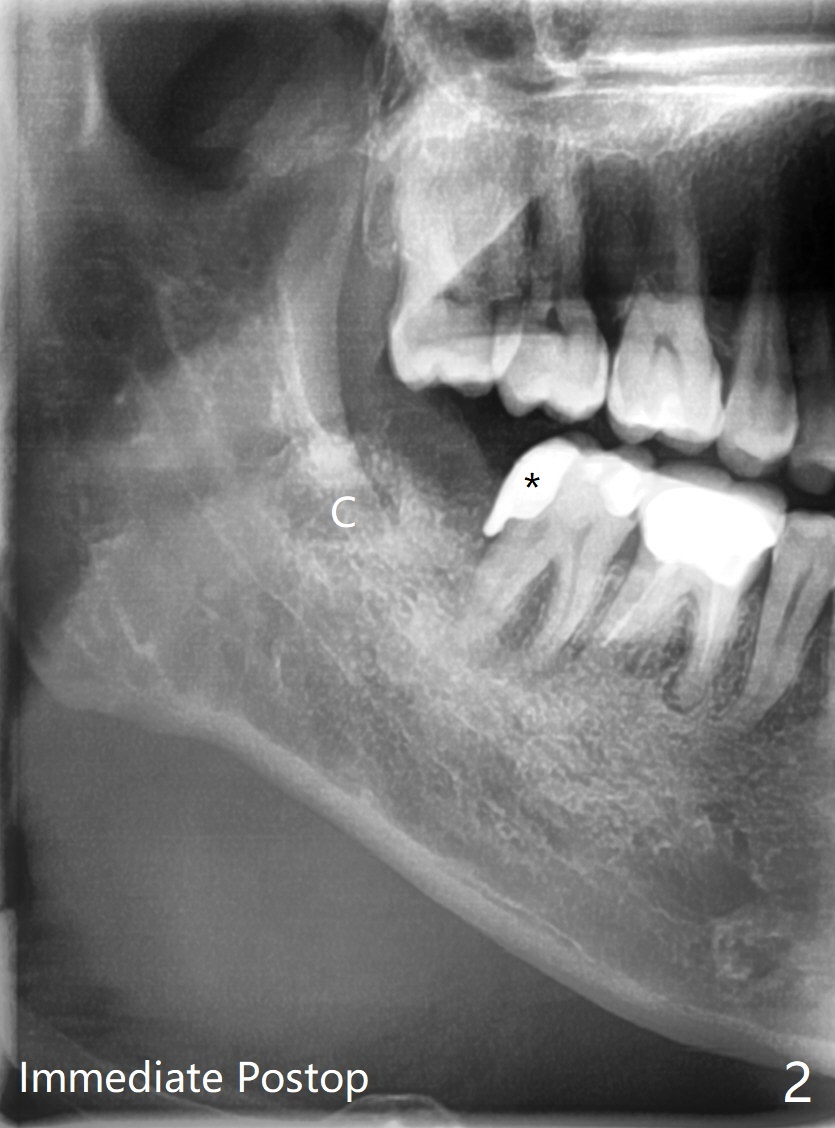

最近放置骨水泥或者胶原塞后连续发生两例干槽症(女51,18岁(去骨))。当57岁男因右下7龋齿夜间痛(图一:*),远中骨质吸收(<)就诊时,提出拔除8后放置粘性骨粉和PRF,他欣然同意。拔除智齿(没去骨,但是劈牙)后,7远中去龋,临时充填(图二:*(IRM,必要时转诊根管治疗))。为了让粘性骨粉在最关键部位(7远中)发挥作用,放置前在牙槽窝根尖放置胶原塞(C),占据空间,后来发现骨粉量足够。